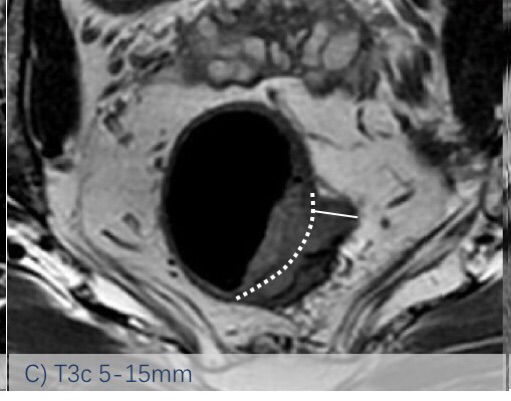

依然采用了2013版的方法,该分类法是基于英国MRC的MERCURRY研究所确立的标准,基于治疗前高分辨率MRI下、按照原发肿瘤突破肠壁固有肌层后侵入直肠系膜内的垂直距离来区分,按1mm,1-5mm,6-15mm,>15mm将T3分为a、b、c、d四个亚组。(图1:A, B, C, D)

图-1: MRI的T3亚分期(A, B, C, D)如下:

图C示MRI影像片上测量T3浸润深度的示意图